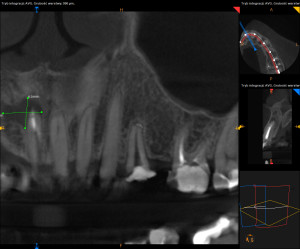

Dokumentacja RTG

- OPG przed zabiegiem wykonane przez lekarza prowadzącego

- RVG

- CBCT przed i po zabiegu